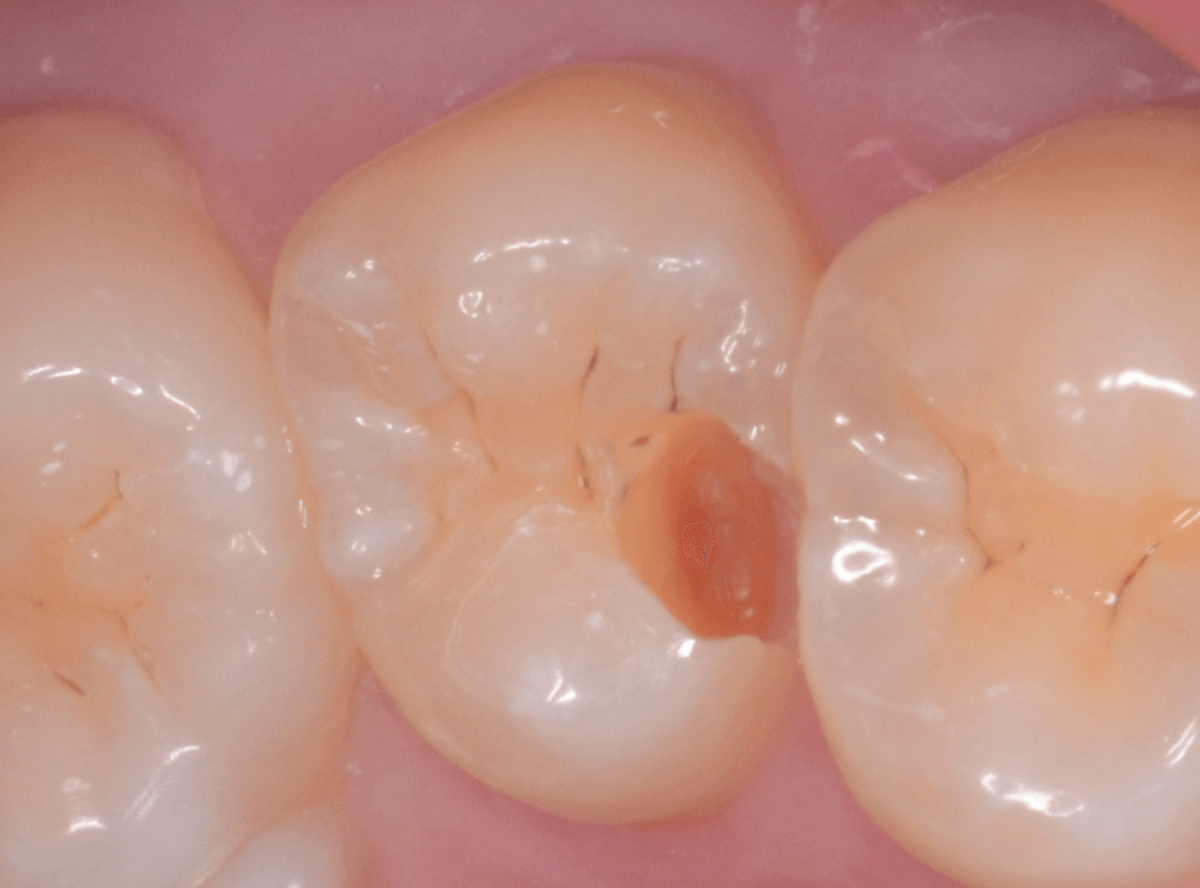

Case.7 レントゲンに写らないレジンの中の虫歯を削って調べる

こちらも定期検診希望で来院された患者さんです。

特に症状はありませんが、歯の咬頭(噛み合わせの山の部分)に小さな穴が空いていて、その周りがもやっと黒く見え、虫歯が怪しいです。

レントゲン写真で確認しますが、ここでは特に問題はなさそうに見えます。

患者さんに状況を説明し、慎重に削って調べる事になりました。

少しずつ穴の部分を削ってみると、ズブッと落とし穴にはまるような柔らかい虫歯の層(=軟化象牙質)に当たりました。

慎重に虫歯を除去したところです。

歯の溝のレジンが詰めてあった部分まで虫歯は進行していました。

とはいえ、それほど深く虫歯は進行していませんでしたので、虫歯除去後、レジンを充填して治療は終われました。

このように定期的にメンテナンスに来ていただくと虫歯が本格的に進行する前に対処する事ができます。